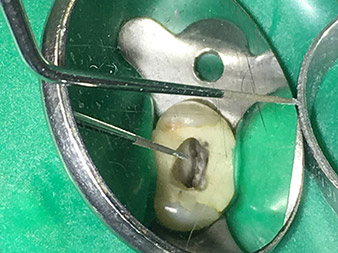

Efficient and atraumatic root canal treatment

Alongside efficient diagnostics and treatment methods, the use of the latest technical aids and instruments also makes an important contribution to successful patient care. Dr Shahrad Nouraie Ashtiani and his team at the practice in Bremen, Germany, treat up to ten endodontics cases a week. Patients’ desires for treatment which is as atraumatic as possible combined with good prognoses for success present a daily challenge for the dentist and oral surgery resident specializing in endodontics.

As an avid user of the expanded W&H instrument range for ultrasonic endodontics, Dr Nouraie Ashtiani is not only able to perform root canal treatments more efficiently but also to do so in a way which puts less strain on the patient. The dental expert masters even the most difficult of situations with ease. In a recent interview, the specialist in endodontics told us about the particular features which characterize the W&H instruments and mentioned possible risks which can arise in root canal treatment.

Pictures: Dr. Shahrad Nouraie Ashtiani, Bremen